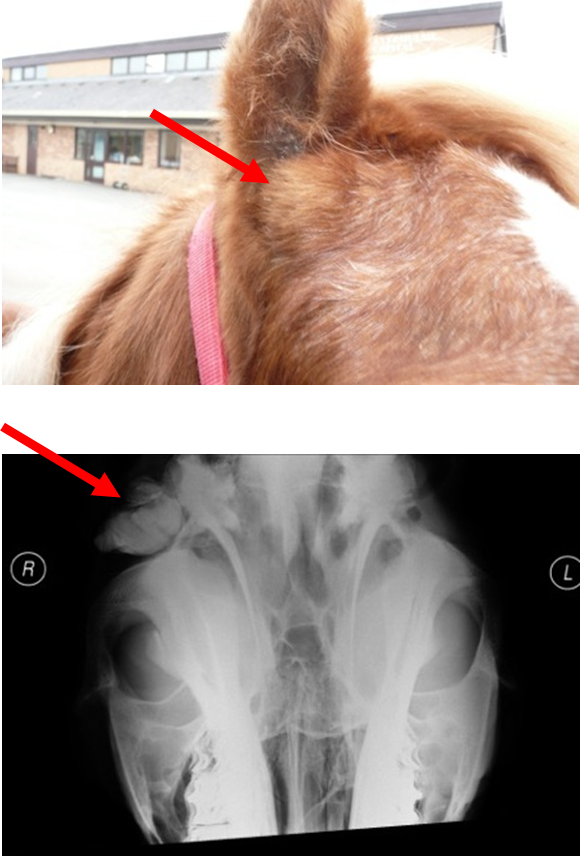

What is dentigerous cysts?

Congenital condition —> failure of closure of 1st branchia cleft

Swelling on head —> usually @ base of ear, firm ± discharging sinus tract but can occur elsewhere (rare)

How are dentigerous cysts diagnosed?

Clinical signs, rads, CT

How are dentigerous cysts managed?

Can be left untreated

Usually removal requested cosmetically —> risk of infection developing / problems selling horse

Describe surgical excision of dentigerous cysts

Performed under GA

Advanced & specialist

Prognosis good —> no cyst remnants should be left in situ